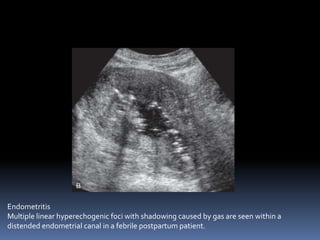

This document contains an image gallery from Dr. Mohit Goel showing various uterine anomalies and ovarian cysts. It includes images of an arcuate and unicornuate uterus, endometritis, a twisted ovarian pedicle, dermoid cysts of varying sizes and echogenicity containing hair, fat, and calcifications, and a combination dermoid cyst showing both mesh and plug structures. The gallery provides ultrasound images of different gynecological conditions for medical education and reference.